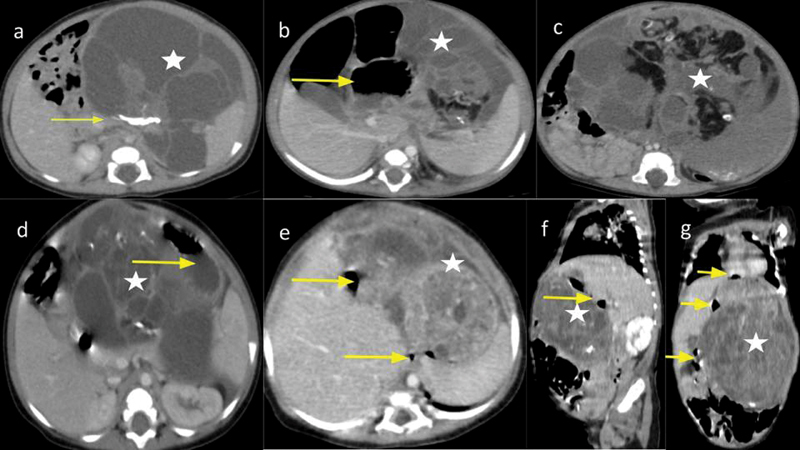

Gastric teratomas are an extremely rare variety of teratomas in children. The aim of our series is to present the natural history and progression of the disease. Retrospective analysis of prospectively maintained data of all the gastric teratoma patients treated at our center was done from their electronic medical records. A total of four cases of gastric teratoma were found to have been treated, all of them being less than 1 year old with three-fourths being male. Typical imaging features of teratoma along with normal germ cell tumor markers helped in making a diagnosis. Surgery is the main form of treatment. In final histopathology, there was equal distribution of mature and immature teratomas. On long-term follow-up, there has been no incidence of recurrence. There needs to be reporting of more cases to verify its natural history.